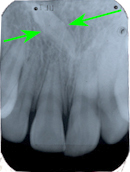

Ein 32 Jahre alter Mann kommt im November 1984 mit Zahnweh am unteren linken, zweithintersten Molaren (Backenzahn) in die Praxis. Das Röntgenbild von Abb. 1 zeigt insuffiziente Wurzelfüllungen bei allen drei Wurzelkanälen und an den Wurzelspitzen sogenannte Granulome, sichtbar als schwarze Flecken (grüne Pfeile in Abb. 1).

In Abb. 2 ist das Röntgenbild 22 Jahre nach korrekter Wurzelbehandlung mit dem nun überkronten Zahn zu sehen. Der Knochen um die Wurzelspitzen ist entzündungsfrei gesund.